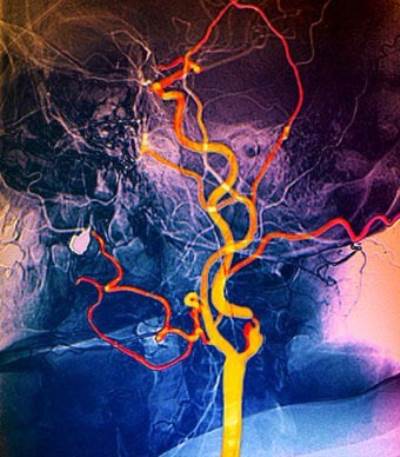

وكما هو معروف فإن هذه العمليات تتم بالكثير من الطرق التي تهدف إلى تصغير حجم المعدة بما لا يؤثر على أداء المعدة لوظيفتها الأساسية، وهي هضم الطعام، وذلك من خلال عدة تقنيات، منها على سبيل المثال عمل ما يشبه الرباط حولها، وهو ما يسمى بالعامية «ربط المعدة» أو من خلال استئصال جزء منها أو من خلال تحويل مسار الطعام، بحيث لا يمكث فترة طويلة في المعدة بعد تقسيمها إلى جزأين وتشريح الأمعاء الدقيقة وربطها بكلا الجزأين.